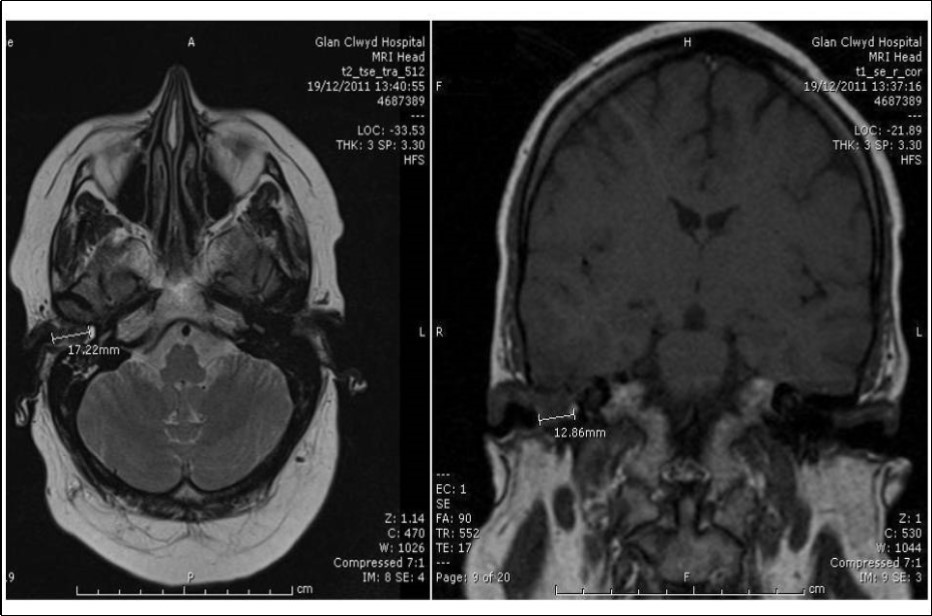

She had CT and MRI of her head. The CT showed occlusion of right external auditory canal with soft tissue mass with bone destruction superiorly. The soft tissue pushed the tympanic membrane into the middle ear which was itself pneumatised and free of the disease (Figure 3). The MRI detected intracranial extension into posterior fossa (Figure 4). She had also CT scan of neck, thorax, abdomen and pelvis for staging that didn’t show further disease.

Figure 4.Axial MRI head showing extension from medial aspect of right EAC intracranially